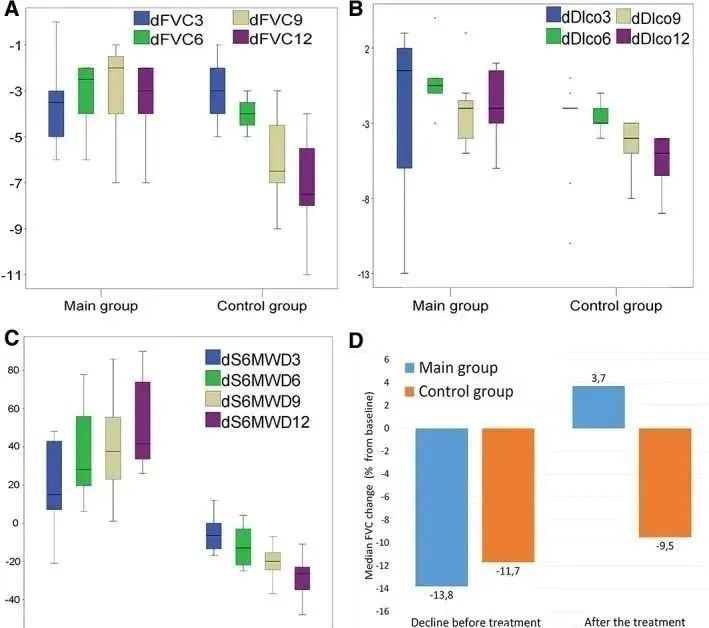

2017年,著名期刊《Chest》在線發表了一項關于同種異體人間充質干細胞治療特發性肺纖維化安全性臨床試驗。9例輕度至中度特發性肺纖維化患者分成三組,靜脈輸注不同濃度的間充質干細胞。60周后的評估結果表明未發生嚴重不良事件,證明了間充質干細胞輸注治療輕、中度特發性肺纖維化的安全性。